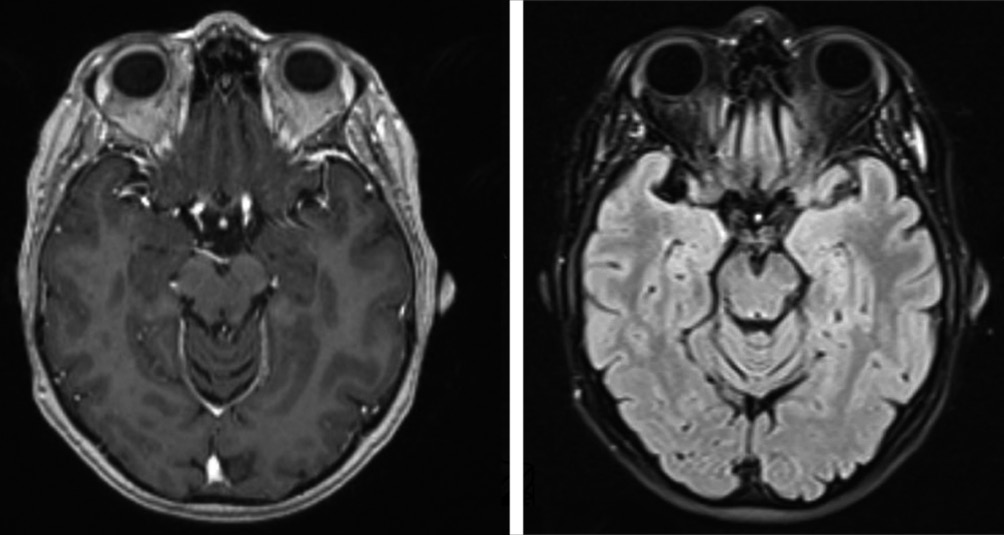

Выполнена магнитно-резонансная томография (МРТ) головного мозга с контрастированием от 13.03.2019. В белом веществе лобных и височных долей, субкортикально и паравентрикулярно — до 10 очагов гиперинтенсивного по T2 и FLAIR сигнала размерами от 0,2 см до 0,6 × 0,3 см и очаги без чётких контуров за счёт перифокального отёка. После введения контрастного вещества сразу и через 20 мин в отсроченную фазу усиления интенсивности сигнала от выявленных очаговых изменений не определяется (рис. 1).

Рис. 1. МРТ головного мозга пациентки С. в режимах T2 (А) и FLAIR (В) от 13.03.2019. / Fig. 1. Brain MRI of patient S. — T2-weighted (A) and FLAIR sequences (B), 13.03.2019.

Повторно была назначена МРТ головного мозга с контрастированием от 10.01.2020 для исключения симптоматики паркинсонизма на фоне демиелинизирующего процесса (рис. 3).

Рис. 3. МРТ головного мозга пациентки С. в режимах Т1 и T2 от 10.01.2020. / Fig. 3. Brain MRI of patient S. — T1-weighted and T2-weighted sequences, 10.01.2020.

На МРТ, взвешенных по Т2: TSE — 3,0 мм в аксиальной проекции, FLAIR FS — 0,9 мм в аксиальной проекции, T13D — 0,9 мм; при DWI и режиме SWI визуализированы суб- и супратенториальные структуры. Срединные структуры не смещены. Дифференцировка серого и белого вещества удовлетворительная. В шишковидной железе имеются мелкие кисты размерами до 0,2–0,3 см. В белом веществе лобных и височных долей, субкортикально и перивентрикулярно — менее 10 очагов гиперинтенсивного по T2 и FLAIR сигнала размерами от 0,2 см до 0,6 × 0,3 см и очаги без чётких контуров за счёт перифокального отека. Боковые желудочки мозга не расширены, симметричные, размер желудочков на уровне отверстий Монро 0,6 см с обеих сторон. III желудочек шириной до 0,5 см. IV желудочек и базальные цистерны не изменены. Хиазмальная область без особенностей. Ткань гипофиза высотой до 5 мм, верхний контур несколько вогнут, МР-сигнал однородный. Супраселлярная цистерна не расширена. Сигнал от зрительных нервов обычный. Слуховые нервы обычной толщины, структура однородная. Субарахноидальные конвекситальные и межгиральные пространства расширены преимущественно в области лобных, теменных долей и сильвиевых щелей на фоне атрофических изменений коры больших полушарий и мозжечка. Миндалины мозжечка расположены на уровне большого затылочного отверстия.

После введения контрастного вещества сразу и через 20 мин в отсроченную фазу усиления интенсивности сигнала от выявленных очагов изменений не определяется.

МР-картина наружной заместительной гидроцефалии. Очаговые изменения вещества головного и спинного мозга демиелинизирующего характера.

Таким образом, по данным МРТ головного мозга с контрастированием, очаги располагаются в субкортикальной и перивентрикулярных областях, очаги демиелинизации не затрагивали структуры экстрапирамидной системы, что исключает непосредственное воздействие очагового демие- линизирующего процесса на синдром паркинсонизма.